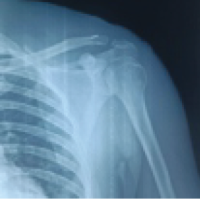

A 6-year-old school-going female child sustained trauma to the right forearm due to a fall on the outstretched hand, resulting in a closed injury in August 2021. Plain radiography of the elbow revealed right proximal ulna and radius fracture with radial head dislocation seen in (Fig. 1a). Although initially thought to be type IV Monteggia fracture, upon close observation, it was seen that the radius was fractured proximal to the ulna. Hence, as per Bado classification, it was diagnosed as a type I equivalent due to the radial head being dislocated anteriorly (Fig. 1b). The patient had a history of soft tissue injury around the elbow a year back, treated with plaster casting. The current fracture was treated within 48 h, where the radial and ulnar fractures were closed reduced and fixed with intramedullary titanium elastic nailing (TENS) system and the radiocapitellar joint was closed reduced and fixed with a K-wire. However, following surgery, it was observed that radiocapitellar joint was dislocated as seen in (Fig. 1c).

Figure 1: (a and b) Plain X-rays of the elbow showing proximal radius and ulna fracture with anterior dislocation of the radial head. As the radius is fractured proximal to the ulna, it is a type I equivalent under the Bado classification. (c) Post-operative X-ray showing persistent dislocation of radial head. (d) A single incision is made to expose both the radial head and the ulna shaft. The posterior interosseous nerve is identified. (e and f) The radio-capitellar joint is fixed to improve the rotational stability of the radius. (g) The wire is removed at 3 weeks, showing a stable joint. (h and i) At 3-year follow-up the elbow is stable, with limited pronation.